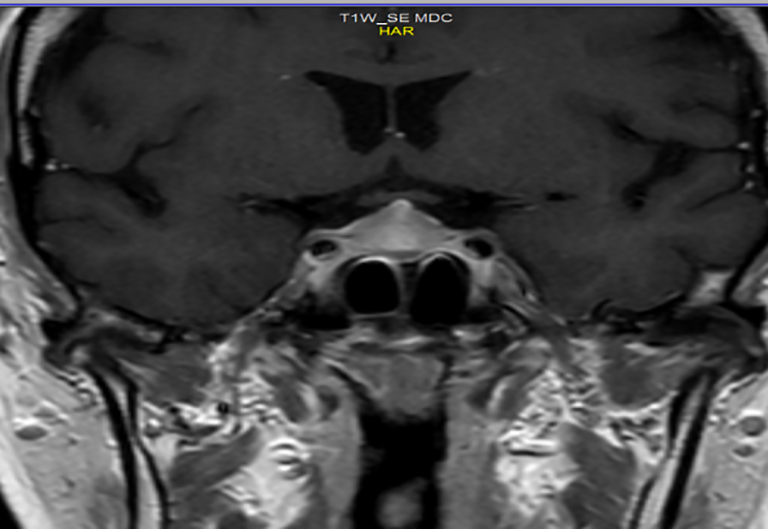

In December 2020, the patient had G2 asthenia, restriction of activities of daily living but not of personal care, dizziness, headache, non-alterations of vision, and G1 diarrhea. Laboratory tests showed hypoglycemia (72 mg/dl), hyponatremia, reduced levels of ACTH (5.4 pg/ml; normal range 7.2–63.3 pg/ml), and cortisol (3.5 µg/l; normal range 23–194 µg/l) at 8:00 a.m., TSH (0.18 µUI/ml), and FT4 (0.6 ng/dl). The ACTH stimulation test (1 µg) showed an insufficient adrenal response (basal cortisol: 3.3 µg/dl; cortisol 60 min: 6.8 ug/dl). Due to the headache and dizziness, a magnetic resonance imaging (MRI) of the brain was performed and highlighted the radiological signs of a meningeal irritation attributable to an hypophysitis (Figure 2).

Figure 2 MRI: Radiological signs of hypophysitis. Inhomogeneous and enlarged appearance of the pituitary gland showing “tent” morphology due to tension of the meninges with thickening of the pituitary stalk.

Then, in the presence of secondary adrenal insufficiency and secondary hypothyroidism, a diagnosis of immuno-related hypophysitis was placed, also supported by radiological imaging. The ICI was stopped, and an adrenal and thyroid replacement therapy (levothyroxine, 125 µg in the morning and cortisone acetate 25 mg upon awakening and 12.5 mg in the early afternoon) was administered. The immunotherapy was suspended for a month and resumed after normalization of pituitary function. The patient still maintains a complete radiological response with an OS of 29 months.